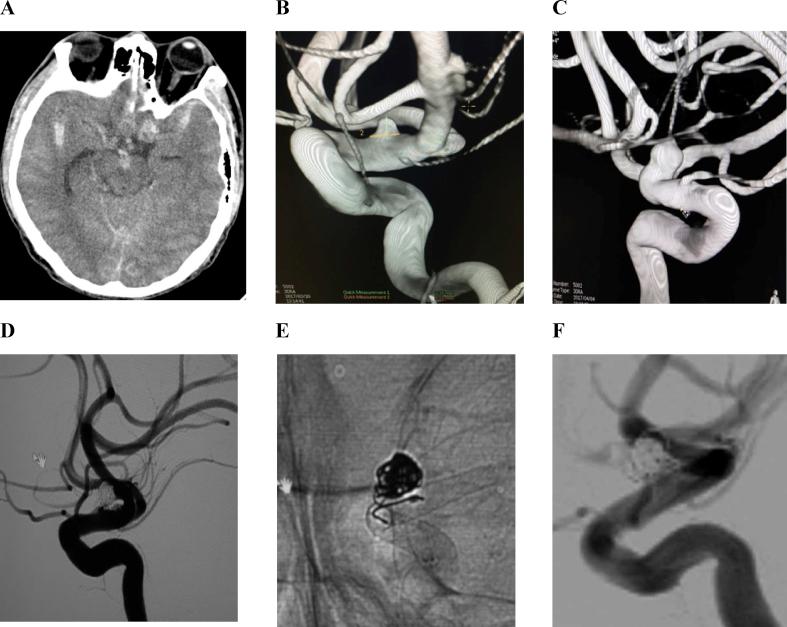

This study was conducted in a consecutive series of 130 patients. 134 procedures were performed for treating these patients in Hanoi Medical University Hospital and Bach Mai Hospital from January 2012 to April 2017. 143 flow diverter stents (Pipeline, FRED and SILK) were used. Aneurysm morphology, stent patency and cerebral parenchyma before and after intervention were analyzed on images of digital subtraction angiography (DSA), computed tomography (CT) and magnetic resonance (MR). The follow-up data after 3-6 months and 12 months were recorded.

In 130 patients (31 men, 99 women), aneurysms of internal carotid artery were mostly common (92.6%), especially in cavernous (35.1%) and in para-ophthalmic (40.3%) segments. 83 cases (61.9%) had wide-neck aneurysms, and 16 cases (11.9%) had multiple aneurysms, and only 5 cases (3.7%) had blister-liked aneurysms. Endovascular treatment was successfully performed at rate of 94.8%. In 3 patients, the stent could not be delivered. Mortality and morbidity rates were 1.5% and 3.7%, respectively. MRI and MSCT follow-up at 3 months showed complete or incomplete occlusions of aneurysms was 7.4% or 17.5%, respectively. 3 patients experienced a thromboembolic event (4.3%).